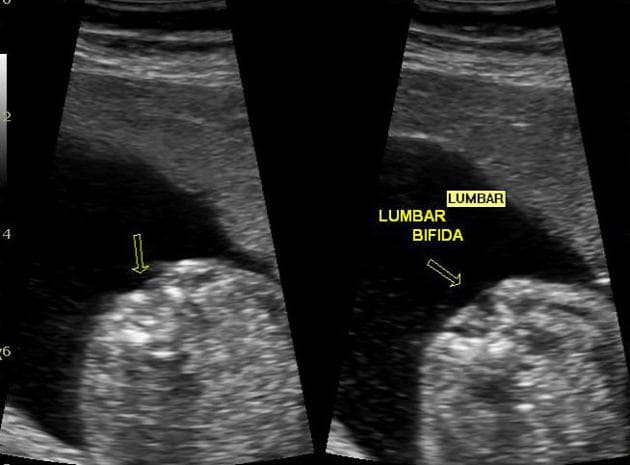

Ca bệnhGai đôi sống ẩn

Gai đôi sống ẩn

Gai đôi sống ẩn (Spina bifida occulta)

- "Gai đôi sống ẩn là một phát hiện tình cờ phổ biến, đặc trưng bởi sự không liền của các cung sau đốt sống."

- "Thường gặp nhất ở mức L5 và S1."

- "Thường không có triệu chứng và không liên quan đến tủy sống hoặc màng não."

Gai đôi sống ẩn là thể nhẹ nhất của khiếm khuyết ống thần kinh. Đặc trưng của nó là sự không liền của các cung đốt sống, thường ở vùng thắt lưng cùng, mà không có sự thoát vị của tủy sống hay màng não. Hầu hết các trường hợp không có triệu chứng và được phát hiện tình cờ qua chẩn đoán hình ảnh. Ước tính tình trạng này xảy ra ở khoảng 10-20% dân số khỏe mạnh. Mặc dù nhìn chung là lành tính, đôi khi nó có thể liên quan đến các dạng loạn sản cột sống khác nếu có các dấu hiệu ngoài da (như túm lông hoặc lúm đồng tiền).